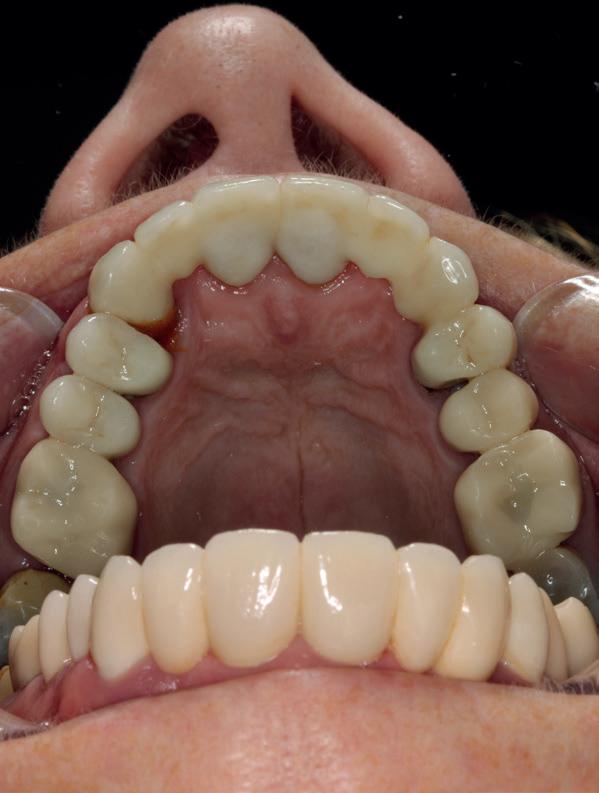

In de prothetische fase (zie foto’s) is in de bovenkaak gebruikgemaakt van verschroefde zirconia bruggen, die enkel buccaal zijn opgebakken. Deze bruggen zijn verlijmd op individuele, geanguleerde titanium abutments. In de onderkaak is een verschroefde kunststofbrug op een titaniumbasis (wrap-around) gemaakt. Voor deze combinatie is gekozen vanwege een minder hinderlijk tikkend geluid bij functie en kleinere kans op breuk van de keramiek. Een nadeel is verhoogde slijtage van de kunststof elementen, maar deze zijn in de jaren later eenvoudig te vervangen op de bestaande brug. Ondanks alle digitale mogelijkheden is de afdruk en registratiefase analoog uitgevoerd, omdat in ervaring van de behandelaren dit bij deze totale rehabilitaties op implantaten nog altijd de grootste precisie oplevert. Er is afgedrukt met impregum in individuele lepels en de pasvorm is gecontroleerd met rigide duralay bars. De relatie wordt vastgelegd zoals bij een volledige prothese met waswallen en pijlpuntregistratie. De opstelling in was wordt gepast en laatste correcties worden gemaakt in samenspraak met de patiënt, de restauratieve tandarts en de tandtechnicus. Na het vastzetten van de suprastructuren worden de schroefgaten afgesloten met composiet.

Patiënt G. is ingedeeld in een recall fase van eens

10. In de bovenkaak is gekozen voor 3 zirconium bruggen; in de onderkaak is gekozen voor een wrap-around met titanium

core.

11. In de bovenkaak is keramiek gebruikt en in de onderkaak kunststof (behandeling is

in de zes maanden bij de mondhygiënist voor peri-implant reiniging, pocketmetingen, mondhygiëne instructies en controles. De AirFlow wordt daarbij standaard gebruikt. Verder wordt de patiënt na één, drie en zes jaar gezien voor controle van de suprastructuren door de restauratieve tandarts. Uit de röntgenfoto’s kan afgeleid worden dat het botniveau gelijk blijft over tijd. Klinisch ziet de situatie er infectievrij uit; de patiënt onderhoudt het zelf netjes met ragertjes, een elektrische tandenborstel als ook de Waterpik.